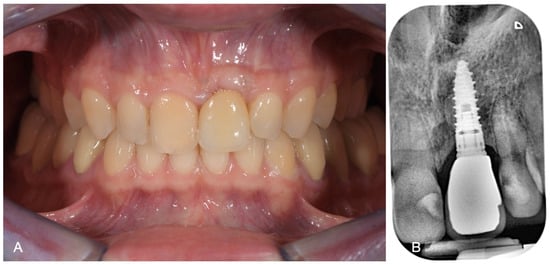

2. Case Report